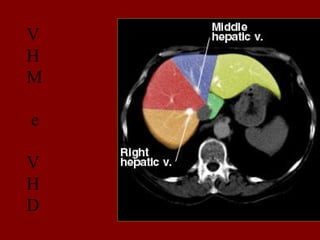

INCISÃO SOBRA A VEIA HEPÁTICA DIREITA

INCISÃO SOBRE A VEIA HEPÁTICA MÉDIA.

INCISÃO SOBRE A VEIA HEPÁTICA ESQUERDA.

V

H

M

e

D